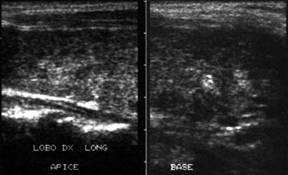

Apexul lobului drept, proiectie longitudinala si trasversala.

Femeie 58 ani. Maladia Graves in tratament cu

metimazol.

Nodul unic in apexul lobului drept, de 11x14x20mm (1,5 cc), hipoecogen, cu

contur difuz

Nu s-a efetuat citoaspiratie.

Aceeasi pacienta. La ecodoppler color - vascularizatie

periferica, avascular intralezional.

Ecopowerdoppler confirma absenta vascularizatiei interne.